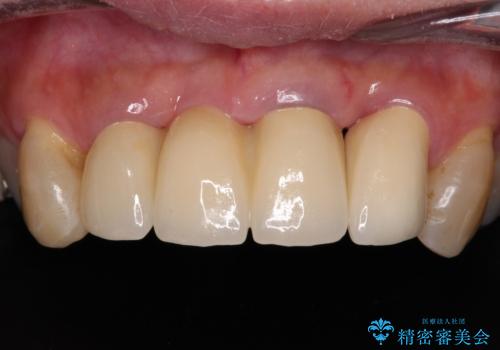

また、前歯に抜歯が必要な歯があったため、抜歯をし、傷の治りを待ってオールセラミックブリッジにて補綴治療を行うこととしました。

一番気になっていた隙間が埋まり、不快感から解放されました。